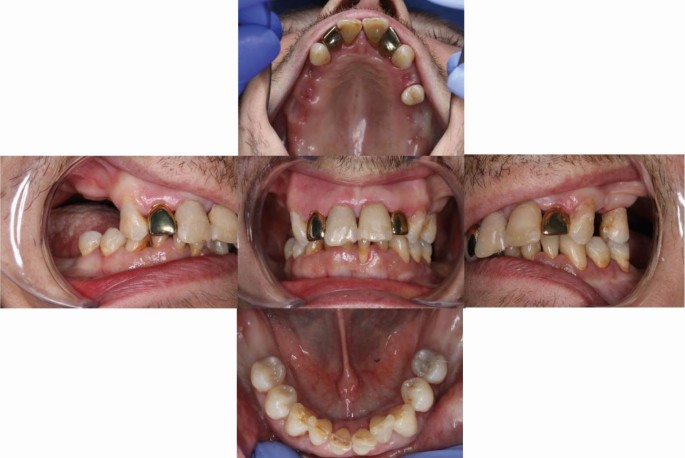

A treatment plan was discussed with the patient and the complexity of treatment and the need for multiple dental visits were explained. The disease control phase of our treatment plan involved dietary advice, oral hygiene instructions, a smoking cessation programme, prescription of Colgate Duraphat toothpaste 5,000 PPM, extraction of unrestorable teeth, scaling and root surface debridement, and restoration of decayed teeth. The patient was also advised to drink plenty of water and use sugar-free chewing gum to improve oral hydration. The rehabilitation phase involved replacement of missing teeth with a modified acrylic partial denture, and the patient was planned for a six-monthly dental maintenance programme (Fig. 3).

During follow-up visits, the patient showed better cooperation with the dental team and accepted scaling, root surface debridement, and fluoride varnish application without the need of any adjunctive sedation. Given the risk of fracture and aspiration of the small acrylic denture fabricated during the early phase of treatment, we decided to add some of the gutta percha cones to the acrylic teeth and to the base of denture with some metal wire (Fig. 4). A cobalt-chromium denture will be constructed in the future to provide a safe and more resistant oral prosthesis in case of an epileptic fit. Patient consent was obtained before all procedures and photographs.

A modified upper partial denture with some gutta percha cones added to the acrylic teethto the base of denture to facilitate identification of denture's parts in case of aspiration during an epileptic fit. Upper lateral incisors were veneered with gold crowns of the extracted teeth per patient's request